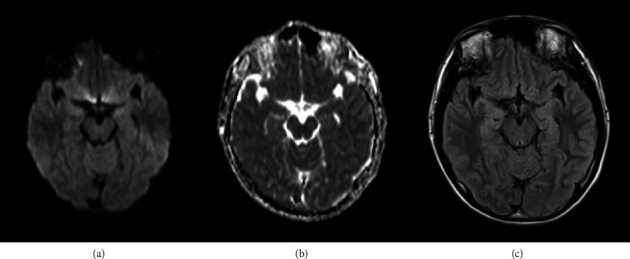

Abstract Image